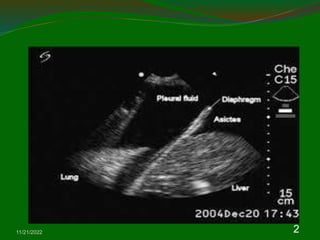

4. Pleural disease

4.1. Pleural effusion

For the purpose of investigation pleural fluid can

be divided into three broad categories according

to etiology: infective, malignant and

miscellaneous.

The infective etiologies result in either a para-

pneumonic effusion or an empyema.

Malignant effusions are due to primary or

secondary thoracic disease, which may be

pulmonary or pleural.

Whereas approximately 500 ml of pleural fluid is

required before an effusion can be identified

clinically, as little 200 ml will blunt the

costophrenic angle.

US in either a standing or sitting position not only

is able to detect smaller volumes of pleural fluid

than the erect frontal chest radiograph but it also

gives useful information about the nature of the

effusion.

The pleural effusion images in ultrasound

appearances are characterized by an echofree

space between the visceral and parietal pleura

.